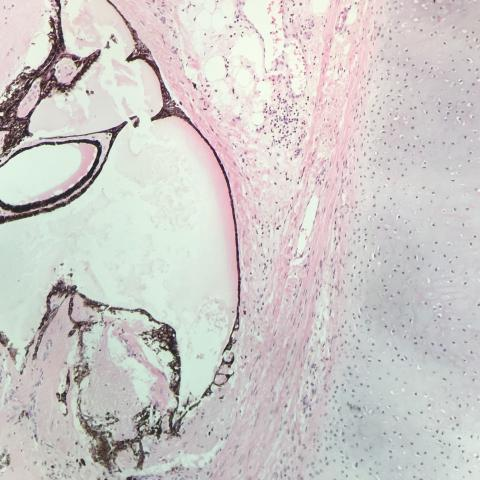

图5 切除标本组织学切片发现,标本与畸胎瘤一致。具有丰富的神经胶质和脂肪,无其他生殖细胞瘤成分,无体细胞恶性转化迹象。切除边缘清晰,切除已经完成。

图6 进一步组织学切片,证实如CT扫描所见的畸胎瘤